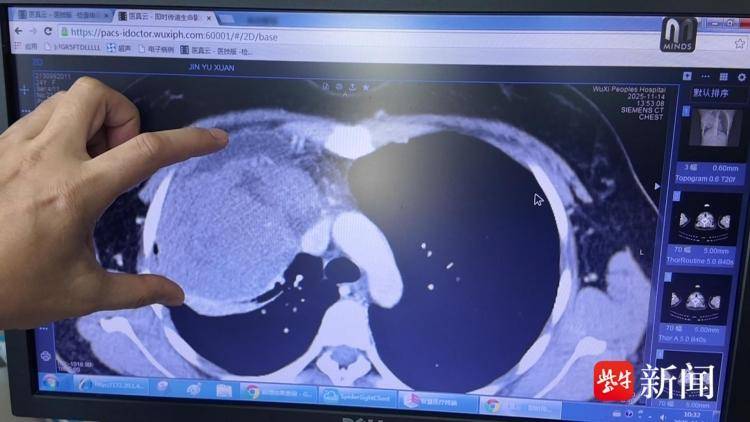

如果不是一次体检,20岁的姑娘吕艾(化名)至今也不会发现自己的胸腔内长了一个小孩头那么大的肿瘤,且肿瘤的位置长得非常刁钻——“趴”在心脏上,“粘”在肺上。如何处理?这一难题交给了南医大附属无锡人民医院胸外科团队。

记者了解到,该肿瘤几乎与上腔静脉、心、肺粘在一起。切除肿瘤是治疗的唯一办法,但是面对如此巨大和位置刁钻的肿瘤,胸外科团队不敢半点懈怠。主任郑明峰介绍,“手术难点之一是肿瘤太大,医生打开胸腔后用肉眼几乎找不到分离的边界。这要求医生对胸部的解剖组织非常熟悉。其次,肿瘤与心肺粘在一起,分离期间一旦血管破裂,要有能力精准判断下阻断钳的位置,迅速缝合止血。医生必须具备非常高的血管成型或血管重建技术。”

目前,小吕已经进入康复期。无疑,她的救治得益于体检。“肿瘤长在女孩胸腔前纵膈的位置。”郑明峰解释,“人的胸腔里除了心、肺等脏器外的其他地方都叫纵膈,人体重要的血管、主动脉、食管等都要经过纵膈。前纵膈里没有东西,属于相对空的地方,再加上人的胸部缺乏敏感感觉神经,所以长了异物不做CT一般发现不了。”他提醒,体检中胸部CT不可少,可以早发现早治疗。